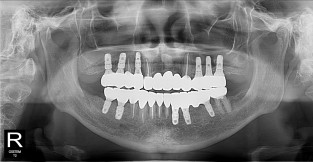

풀케이스

치료기간 : 2022-03-18 ~ 2023-09-15

1. 상기 x-ray 이미지 모두 동일한 해당 의료기관에서 진료한 환자입니다.

2. 상기 x-ray 이미지 모두 동일 인물의 것입니다.

3. 치료 전 이미지는 2022-03-18에 촬영했으며, 치료 후 이미지는 2023-09-15에 촬영하였습니다.

4. 상기 x-ray 이미지 모두 동일 조건에서 환자분의 동의를 받아촬영되었습니다.

* 임플란트 시술은 환자분의 상태(고혈압, 당뇨 등)에 따라 부작용이 있을 수 있으니, 반드시 전문의와 상담이 필요합니다.

* 임플란트 수술 부작용

: 수술 후 출혈, 교합, 통증, 붓기, 염증 등의 문제점이 발생할 수 있습니다.)